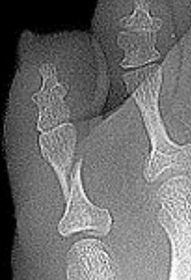

| What type of fracture is shown at the 2nd metatarsal? | Transverse fracture |

| What type of fracture is this? | Oblique fracture |

| What type of fracture is this? | Spiral fracture |

| What type of fracture is this? | Comminuted fracture |